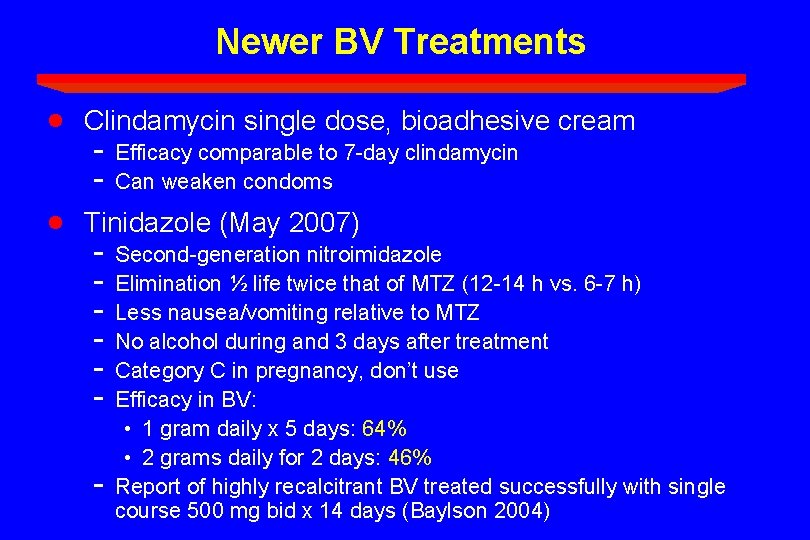

Newer BV Treatments · · Clindamycin single dose, bioadhesive cream - Efficacy comparable to 7 -day clindamycin Can weaken condoms Tinidazole (May 2007) - Second-generation nitroimidazole Elimination ½ life twice that of MTZ (12 -14 h vs. 6 -7 h) Less nausea/vomiting relative to MTZ No alcohol during and 3 days after treatment Category C in pregnancy, don’t use Efficacy in BV: • 1 gram daily x 5 days: 64% • 2 grams daily for 2 days: 46% Report of highly recalcitrant BV treated successfully with single course 500 mg bid x 14 days (Baylson 2004)